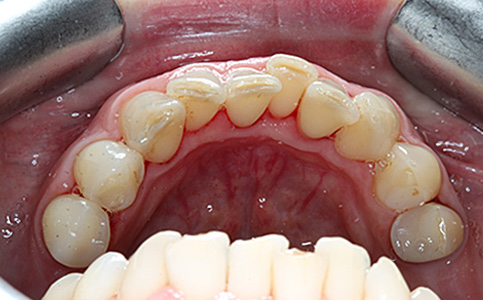

Przykład pełnej rehabilitacji protetycznej obejmujący leczenie biologiczne, uzupełnienie braków zębowych implantami oraz korony pełnoceramiczne w łuku górnym i dolnym. Spektakularna metamorfoza uśmiechu wykonana przez zespół Centrum Stomatologii i Ortodoncji FRESHmed odmieniła życie Pacjenta dodała pewności siebie i sprawiła, że z chęcią się uśmiecha.